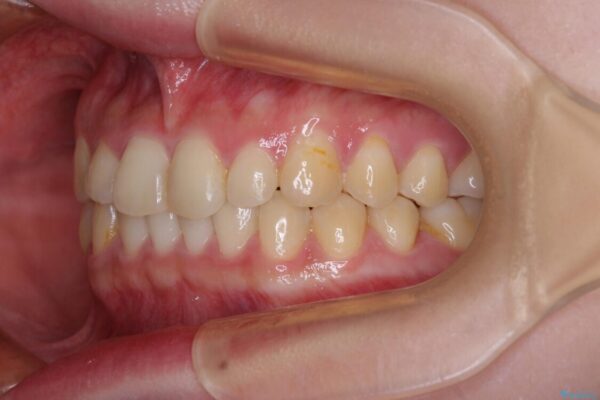

治療後

• 治療途中の奥歯と矯正治療の後戻り インビザライン・ライトによる矯正治療 治療後画像

クラウンはよりよい咬み合わせで装着したいため、インビザラインを1セット使用して概ね歯列を整えた時点で補綴治療を行い、その後仕上げの矯正治療を行いました。